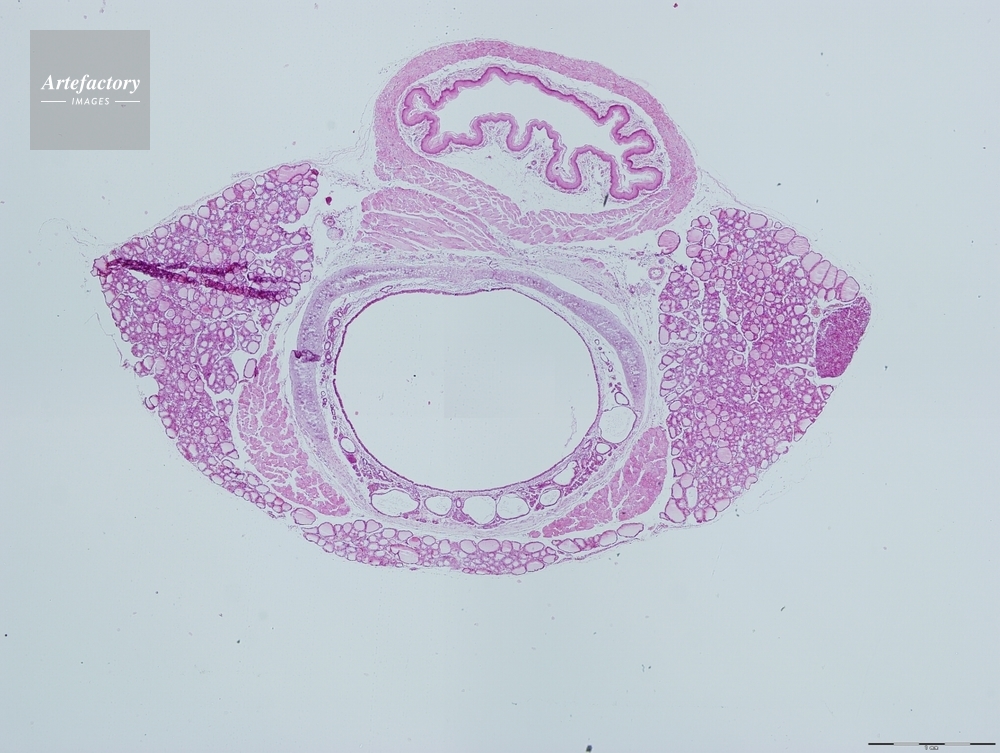

| 作品タイトル | ラット,気管、食道、甲状腺 | モデルリリース | なし | |

| キャプション | 合成画像 | 制限事項 | ||